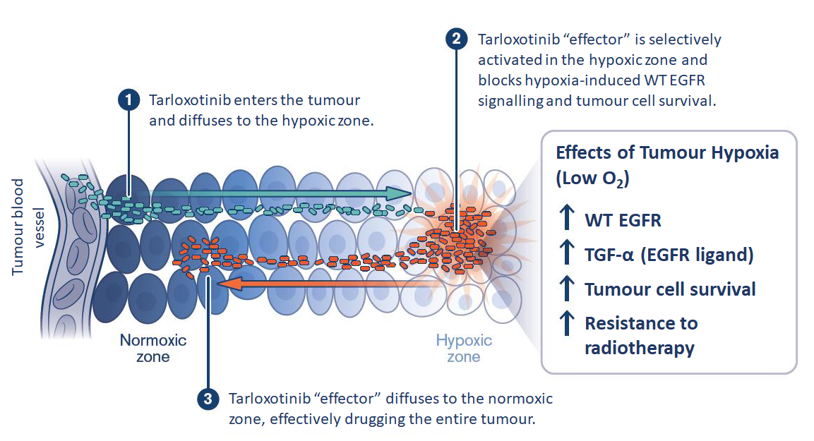

Clinical trials for anti-cancer agent Tarloxotinib

Maurice Wilkins Centre has supported the Tarloxotinib drug development programme over many years. Now, the Phase II clinical stage anti-cancer agent has been acquired by Convert Ph

Turning the tables on cancer

Tumours often contain areas with less oxygen than is found in normal tissues. These areas are less vulnerable to many forms of cancer therapy and often drive development of a more

read the full story

Cancer drug advances to phase II clinical trials

A New Zealand cancer drug developed by two Maurice Wilkins Centre investigators has reached the second phase of clinical trials with patients.